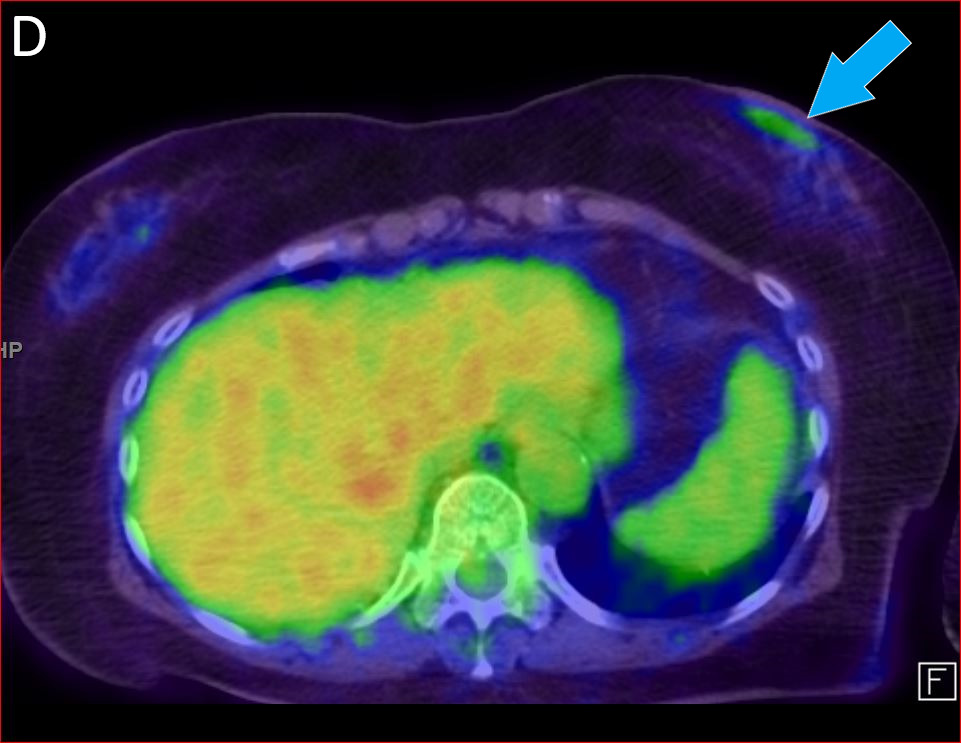

Figure A, coronal CT of the orbits demonstrates infiltrative, enhancing soft tissue in the right orbit (red arrow), predominately intraconal. Figure B, axial CT of the orbits demonstrates the infiltrative enhancing mass in the right orbit which causes enophthalmos (white arrow) compared to the normal left side. Figure C, coronal reformat PET overlaid on the CT orbits which demonstrates abnormal uptake in the right orbit (orange arrow) corresponding to the infiltrative soft tissue mass. Figure D, axial PET/CT demonstrates low-level abnormal uptake in the left subareolar breast (blue arrow). Figure E, clinical photograph demonstrating the enophthalmos and bruising of the right periorbital soft tissues.

The patient was referred to ophthalmology for multiple cranial nerve palsies affecting the right eye, and computed tomography (CT) of the orbit revealing an infiltrative mass encasing the posterior right globe and optic nerve with invasion to the preseptal right orbit. The biopsy of the mass was consistent with metastatic invasive lobular carcinoma (ILC) of the breast. Further evaluation of primary and metastatic disease with a follow-up 18F-fluorodeoxyglucose positron emission tomography (FDG-PET)/CT scan showed a mildly hypermetabolic right orbital mass and very low-level uptake in the subareolar left breast. Of note, ILC does not avidly take up FDG, limiting the sensitivity.1 Furthermore, imaging alone is not adequate to diagnose the etiology of the tumor, as radiological findings of orbital tumors may overlap.2